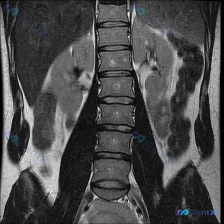

只看这张腰椎MRI冠状位,除了明显的侧弯,还有两个容易漏的关键发现

整理到一张腰椎MRI T2加权序列冠状位的影像资料,先不看后续的其他序列和临床信息,只看这张图的话,有几个点比较值得拿出来讨论: 1. 脊柱力线确实有明显异常,侧弯方向和顶端位置也比较清楚 2. 椎间盘的信号和椎间隙高度有非对称性改变 3. 扫描野里除了腰椎,还能看到双侧肾脏,肾盂肾盏区似乎有信号变...

整理了一张腰椎MRI T2序列冠状位图像的资料,大家可以先看看核心影像表现: - 腰椎整体向右侧凸(凸向右侧,凹向左侧) - 各椎体高度大致正常,边缘可见骨赘形成 - 腰椎下段(L4-L5、L5-S1)椎间隙不对称,凹侧更紧凑 - 冠状位上左侧下方椎间孔区域脂肪信号略显模糊,空间受限 没有提供患者的...

整理到一份腰椎MRI-T2冠状位的影像资料,第一眼就能看到明确的脊柱侧弯——腰椎呈C型向左侧凸。 但仔细看还有几个点: 1. 侧弯凸侧(右侧)椎体边缘有不同程度骨赘形成 2. 双侧小关节增生明显,关节周围有高信号 3. 椎间隙左右不对称,凹侧(左侧)椎间孔空间看起来受压缩 4. 目前层面没看到明确的...

整理到一份腰椎MRI T2冠状位的影像资料,大家先看一眼: 核心影像表现: - 腰椎明显向左侧弯曲,呈“C”型,顶点在腰椎中部 - 椎体形态基本完整,未见明确骨质破坏或压缩 - 椎间盘T2信号普遍减低(偏暗),提示脱水退变 - 侧弯节段椎间隙左右不对称:右侧张开,左侧闭合 - 两侧旁椎肌肉(腰大肌、...

整理到一份腰椎MRI T2序列冠状位的影像分析,第一眼确实很容易被「脊柱侧弯」抓住注意力——影像上腰椎序列明显向左侧弯,多节段椎间盘T2信号减低,椎间隙左右不对称,典型的退行性改变表现。 但再看下去,右肾区有一个圆形的T2高信号灶,报告里单独提了这个「除脊柱以外最显著的异常发现」。 如果只看到前期的...

整理到一份影像读片资料,有点意思,放出来讨论下。 先看核心发现: - 腰椎MRI T2冠状位:明显向左侧凸畸形;椎体边缘骨赘形成,部分椎间隙非对称性变窄;凹侧椎间孔区域相对狭窄。 - 额外发现:右侧(图像左侧)肾脏内见边界尚清的明显高信号影。 影像科初步分析里提了“退行性脊柱侧弯”的依据很足,但同时...